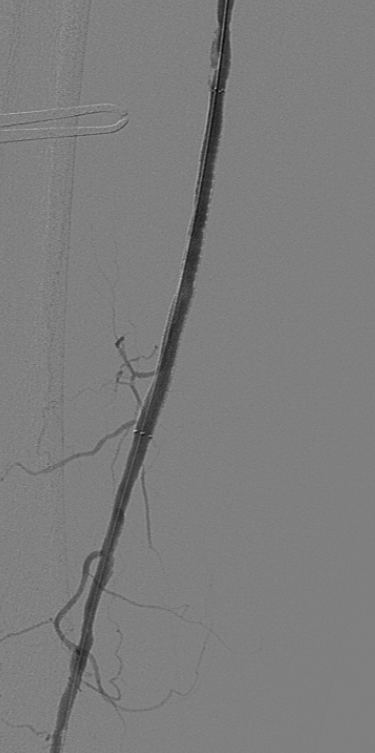

顺行穿刺无法开通,行左侧腘动脉逆行穿刺,超选进入顺行导管。

球囊扩张全程血管,显示支架内有陈旧性血栓,予6F导管吸栓,最后造影显示血流较前通畅,部分附壁血栓继续抗凝治疗,定期随诊。予Exoseal封堵穿刺点。